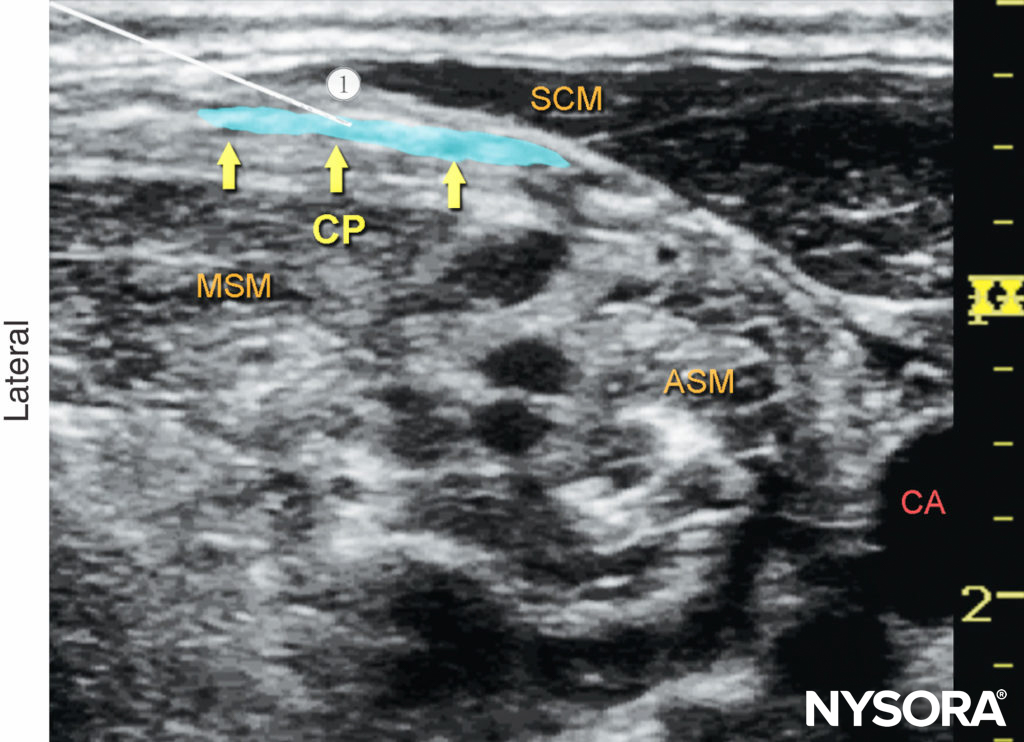

Once the plexus has been identified, the needle is passed through the skin, platysma, and investing layer of the deep cervical fascia, and the tip is placed adjacent to the plexus (Figure 8). Because of the relatively shallow position of the target, both in-plane (from the medial or lateral sides) and out-of-plane approaches may be used. Following negative aspiration, 1–2 mL of local anesthetic is injected to confirm the proper injection site. The remainder of the local anesthetic (5–15 mL) is administered to envelop the plexus (Figure 9).

Figure 8. Superficial cervical plexus (transverse view): needle path (1) and position to nerve block the cervical plexus (CP).The needle is seen positioned underneath the lateral border of the sternocleidomastoid muscle (SCM) and superficial to the prevertebral fascia with the transducer in a transverse position (see Figure 7a). ASM, anterior scalene muscle; CA, carotid artery; MSM, middle scalene muscle.

Figure 9. Cervical plexus (transverse view): desired distribution of local anesthetic (blue-shaded area) to nerve block the cervical plexus. Needle path: 1. ASM, anterior scalene muscle; CA, carotid artery; CP, cervical plexus; MSM, middle scalene muscle; SCM, sternocleidomastoid muscle.